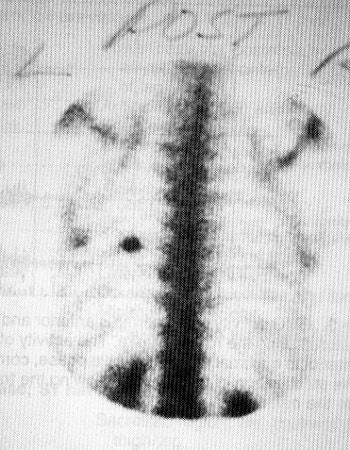

According to Hosea, fractures usually occur between the fifth and ninth ribs, and are typically -- though not always -- located in the posterior lateral corner. Stress fractures don’t appear on x-rays, so nuclear scintigraphy may be the imaging method of choice for identifying these injuries.

| Bone scan shows stress fracture in the rib of a member of the U.S. national and U.S Olympic rowing teams. Image courtesy Dr. Timothy Hosea. |

"There’s a discrete area of increased uptake, a very defined fracture. An intercostal pull has a normal bone scan," Hosea noted.